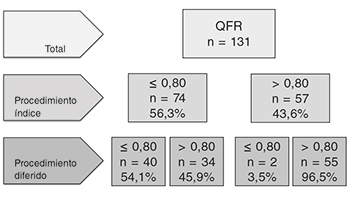

Cambios QFR a lo largo de los procedimientos índice y diferido

Ciento veintidós (93,1%) de las 131 lesiones en vasos no causantes se consideraron aptas para ser sometidas a revascularizaciones percutáneas programadas según valoración visual de la angiografía. De estas, solo el 56,3% arrojaron valores QFR ≤ 0,80 en el procedimiento índice cuando se valoraron retrospectivamente (figura 3). Se pudo confirmar una caída sin relevancia estadística de los valores QFR entre el procedimiento índice y el diferido en pacientes con valores QFR iniciales > 0,80; no obstante, 2 pacientes con valores QFR inicialmente irrelevantes experimentaron una caída < 0,80 en la valoración de la angiografía diferida. Todos los pacientes con valores iniciales > 0,82 confirmaron la presencia de estenosis en el segundo procedimiento. Por otro lado, el 45,9% de las lesiones con valores QFR significativos fueron consideradas irrelevantes cuando fueron valoradas durante el segundo procedimiento, con diámetros medios y áreas estenóticas más grandes (p < 0,001 para ambos) tal y como revela la tabla 2. Los principales cambios observados entre ambos procedimientos se muestran en la figura 4 y en el ejemplo paradigmático de la figura 5. La sensibilidad y especificidad de valores QFR > 0,82 durante el procedimiento índice para predecir estenosis importantes (QFR < 0,80) durante el procedimiento programado fueron del 84 y 58,7%, respectivamente, con un valor predictivo positivo del 52,5% y un valor predictivo negativo del 87% (figura 6). La estrategia terapéutica se implementó con independencia de los hallazgos de la valoración de QFR ya que se hizo una estimación de ésta retrospectivamente. Esto nos permitió comparar la estrategia en base a la interpretación de la valoración de la angiografía visual y posteriores hallazgos QFR en un total de 46 lesiones tratadas con stents a pesar de presentar valores QFR irrelevantes.

Figura 3. Cambios QFR en los procedimientos índice y diferido en pacientes con estenosis significativa confirmada mediante angiografía en vasos no culpables. QFR: ratio de flujo cuantitativo.